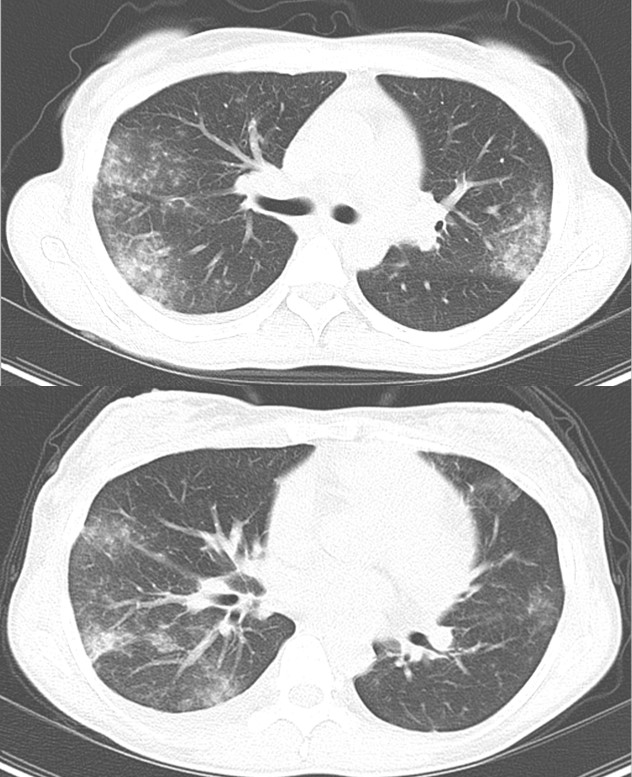

初診時 体幹部CT

- 両肺末梢側優位に小葉中心性に広がる粒状影及びすりガラス影

両肺野のすりガラス影の増悪

初診時

第5病日